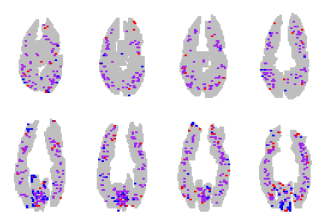

Figure 3 presents a sample of the the sparsity patterns obtained from the different methods, aggregated over all subjects. Red points indicate voxels that contributed positively to picture classification in at least one subject, but never to sentences; Blue points have the opposite interpretation. Purple points indicate voxels that contributed positively to picture and sentence classification in different subjects. The remaining slices for the SOSlasso are shown in Figure 3.

We trained a classifier using 4-fold cross validation on the star plus dataset [20]. Figure 4 shows the discovered sparsity patterns in their entirety for the three methods considered, projected into a brain space that is the union over all size subjects; anatomical data was not available. In each slice, we aggregate the data for all the 6 subjects. Red points indicate voxels that contributed positively to picture classification in at least one subject, but never to sentences; Blue points have the opposite interpretation. Purple points indicate voxels that contributed positively to picture and sentence classification in different subjects.

The lasso with Sparse Overlapping Sets (Figure 4(d)) overcomes the drawback of the Glasso by not forcing all the voxels at a particular location to be active. Also, since we consider groups here, we also tend to group voxels that are spatially clustered. This results is selecting voxels in a subject that are “close-by” (in a spatial sense) to voxels in other subjects. The result is a more clustered sparsity pattern compared to the lasso, and very few ambiguous voxels compared to the Glasso.

The mere fact that we specify groups of colocated voxels does not account for the fact that we discovered clear sparse-group structure. Indeed, we trained the latent group lasso [6] with the same group size ( voxels) and absolutely no structure was recovered, and classification performance was near chance (45% error, relative to chance 50%). It fails because of it’s inflexibility with respect to the voxels within groups. If a group is selected, all the voxels contained must be utilized by all subjects. This forces many detrimental voxels into individual solutions, and leads to no group out performing any others. As a result, almost all groups are activated, and the feature selection effort fails. SOSlasso succeeds because it allows task-specific within group sparsity, and because, by allowing overlap, the set of groups is larger. This second factor reduces the chance that the informative regions of the brain are not well captured in any group.

An advantage of using this dataset is that each subject’s brain was been partitioned into 24 regions of interests, and expert neuroscientists identified 7 of these regions in particular that ought to be especially involved in processing the pictures and sentences in this study [20]. No one expects that every neural unit in these regions behave the same way, and that identical sets of these neural units will be involved in different subject’s brains as they complete the study. But it is reasonable to expect that there will be similar sparse sets voxels in these regions across subjects that are useful to classifying the kind of stimulus being viewed. Because the signal is sparse within subjects, and because spatially similar voxels may be more correlated than spatially dissimilar voxels, standard lasso without multitask learning will miss this structure; because not all voxels within these regions are relevant in all subjects, standard Glasso—even Glasso set up to explicitly handle the 24 regions of interests as groups—will do poorly at recovering the expected pattern of group sparsity. SOSlasso is expected to excel at recovering this pattern, and as we show in Figure 5 our method finds solutions with a high proportion of voxels in these 7 expected ROIs, far higher than the other methods considered.